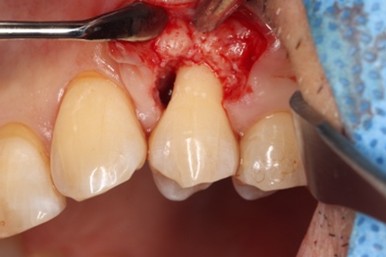

治療中

エムドゲイン®サイトランス®を填入し、レーザーにて血餅形成、縫合

歯周基本治療後に再評価し、ポケットが残存したのでEr:YAGレーザーを併用した歯周組織再生療法(エムドゲイン® 、サイトランス®を使用)を行ったケース

歯周病の好発部位である上顎第一小臼歯近心面における骨吸収に対して再生療法を行ったケース。一般的に根面溝という溝があり歯石の沈着が生じやすい。また溝の存在により術後に歯肉と歯根の付着が生じにくいため、今回はEr:YAGレーザーにて血餅形成を行い組織の安定化を図った。